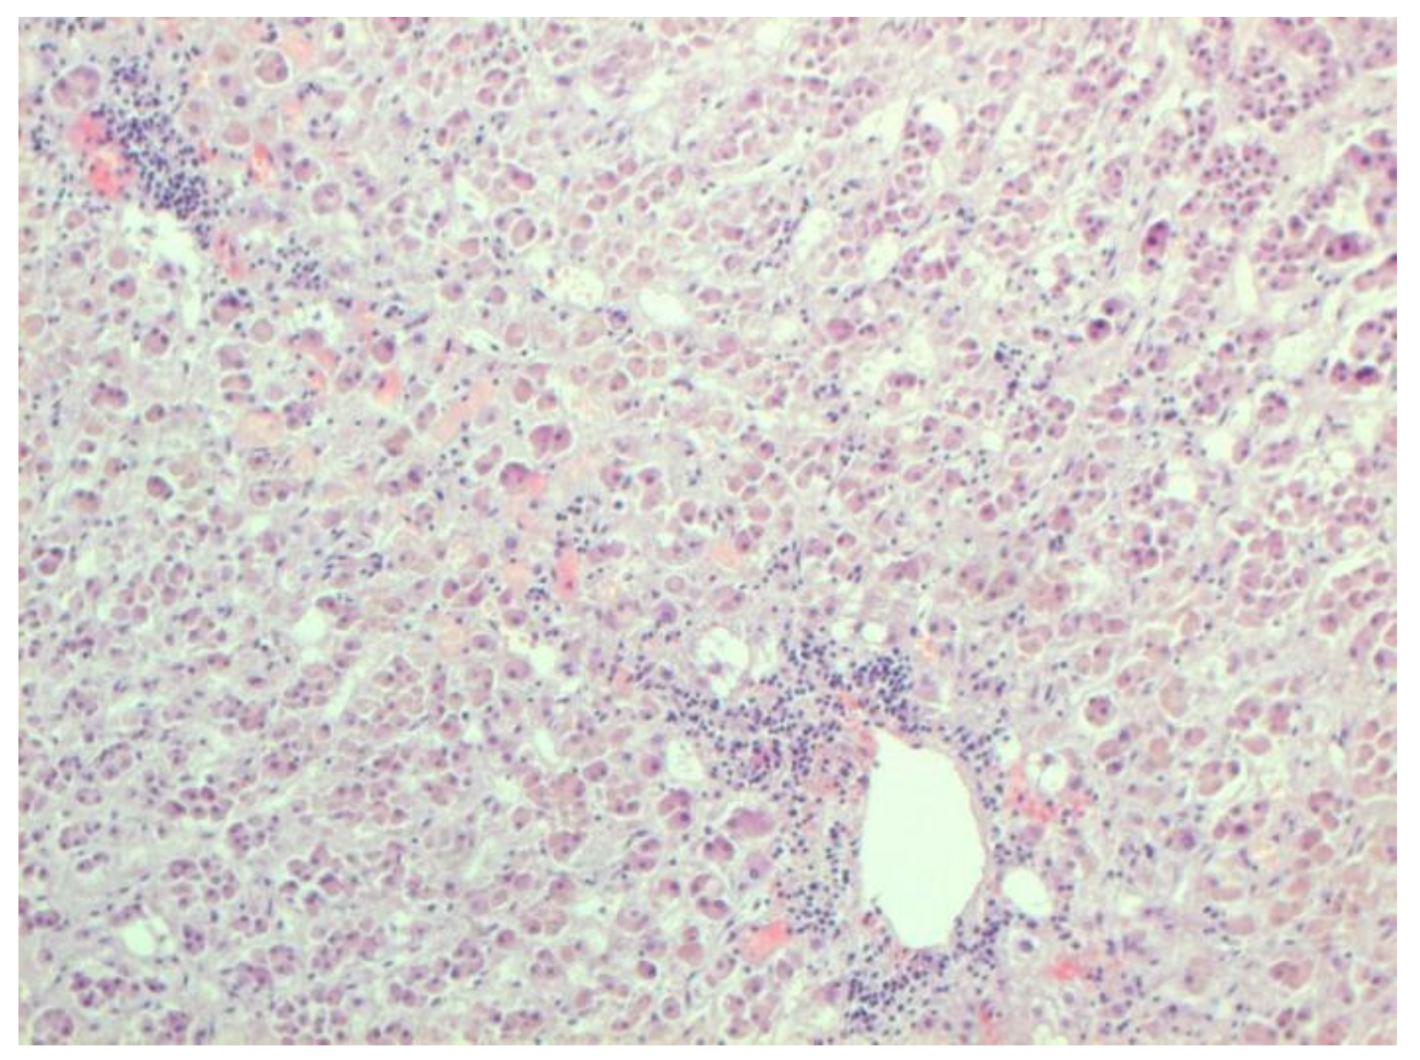

The hallmarks of apoptosis (according to expression of caspase-3) were revealed in the lungs, lymph nodules, and other organs, predominantly in the area with the small granular rhexis (Figure 4 and Figure 5.) The possibility of developing a generalized infection with damage to other organs is evident. Alterative and necrotic changes were seen in parenchymal cells. Sometimes we noted their changes in the nuclei of the cells in the lymph nodes, intestines, soft meninges, heart, pancreas, kidneys, and spleen. We succeeded in detecting spike and nuclear antigen of the virus in the lymph nodes (Figure 6), pancreas, brain (Figure 7), and adrenals. We described certain lesions in the adrenals that are probably associated with the SARS-CoV-2 virus [25].

Figure 4.

Caspase-3 (arrows) in lymph node. ICH ×100.

Figure 5.

Expressed karyorrhexis (arrow) in lymph node. H-E ×200.